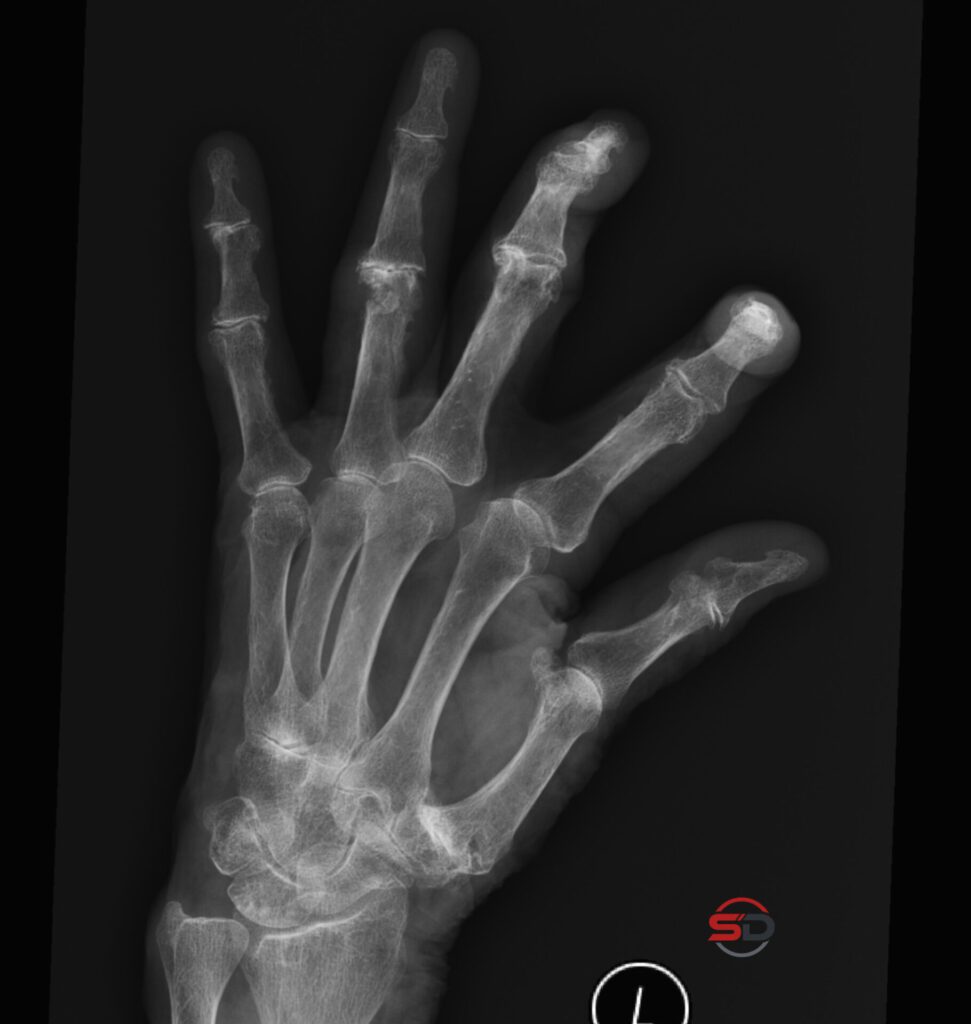

Degenerative und entzündliche Veränderungen der Hand

Degenerative und entzündliche Veränderungen der Hand im Röntgen Die konventionelle Radiographie der Hand ist ein zentrales diagnostisches Werkzeug bei chronischen […]